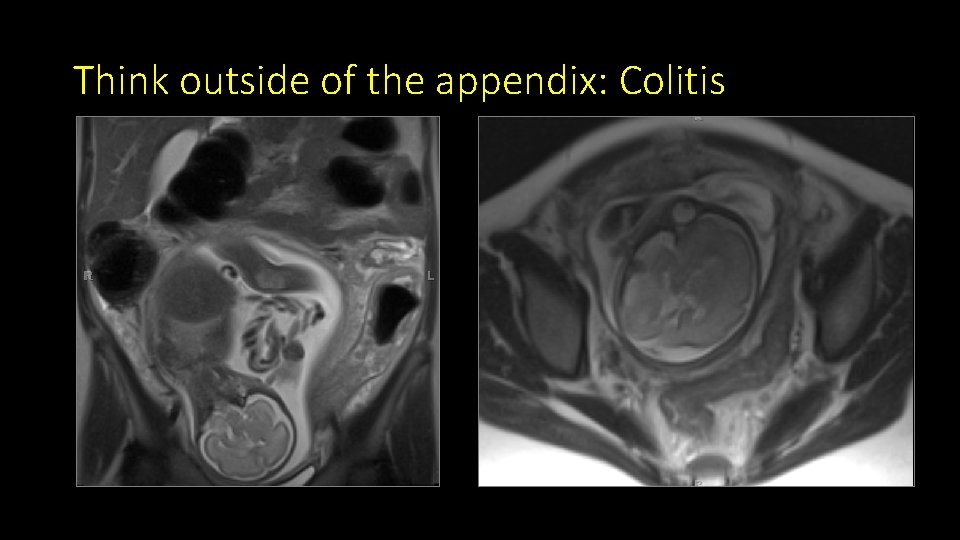

Think outside of the appendix: Colitis